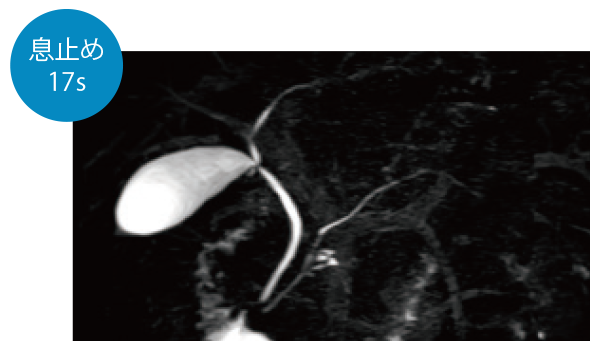

IP-RAPID×DLR Plusによって呼吸同期計測や横隔膜同期計測など時間のかかる検査を短くできます。さらに時間を短くし、息止めによる検査に変更することもでき、患者さまの状況に合わせて検査をお選びいただけます。選択肢が増えるので、検査の幅が広がります。

3DMRCP(息止め)

3DMRCP横隔膜同期(Navi)

3DMRCP(呼吸同期)